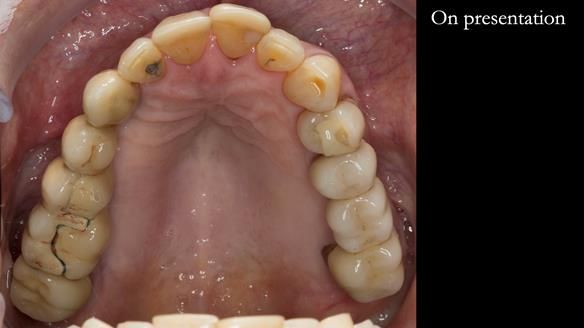

The starting point

We began with the lower jaw.

The upper jaw

In the upper arch:

- a failing upper left tooth supporting a bridge was removed

- an implant-supported bridge on the upper right was dismantled

A metal-based upper RPD was made,

with metal backings incorporated to future-proof the design

should further teeth fail.